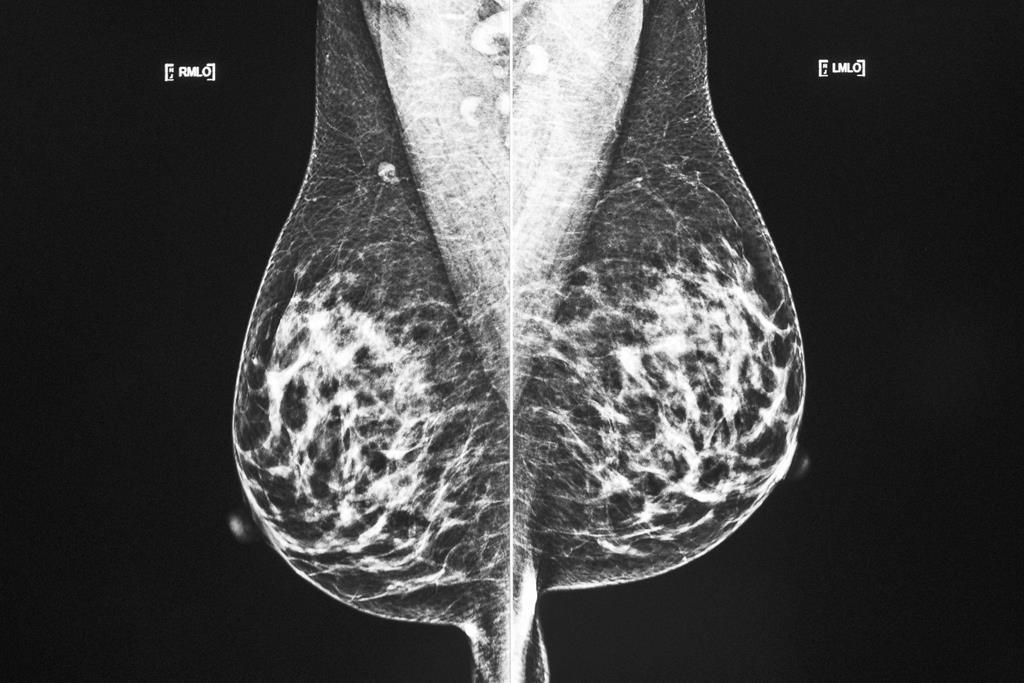

MONTRÉAL — La plupart des femmes qui reçoivent un diagnostic de cancer du sein peuvent maintenant espérer survivre à la maladie pendant plusieurs années, assure une nouvelle étude publiée par le journal médical The BMJ.

Si on sait depuis longtemps que le taux de survie des femmes atteintes d'un cancer du sein s'améliore, c'est la première fois que cette amélioration est mesurée et quantifiée. Pour y parvenir, les auteurs de l'étude ont examiné plus de 510 000 Britanniques touchées par un cancer du sein précoce, dont c'était le premier cancer, qui ont reçu leur diagnostic entre janvier 1993 et décembre 2015, et qui avaient subi une chirurgie.